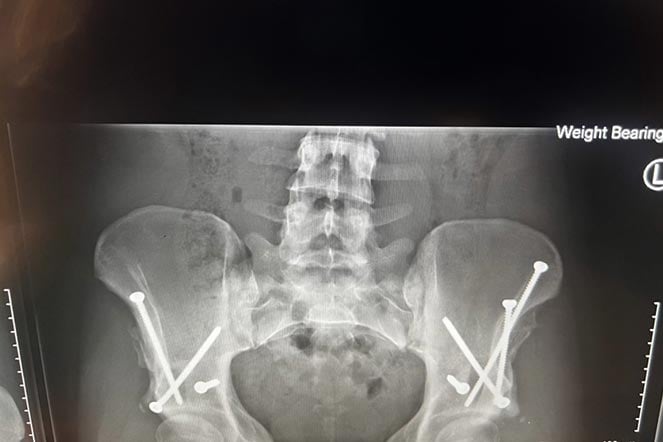

Radiografía de Kiana después de la cirugía